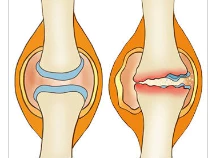

관절염은 뼈들이 만나는 지점인 관절에서 발생하는 질환으로, 이로 인해 관절 연골이 파괴되고 염증이 발생합니다. 이러한 관절은 인체의 움직임을 원활하게 하기 위해 상당히 중요한 구조로, 뼈들의 끝을 덮고 있는 연골은 마치 부드러운 쿠션처럼 작용합니다.

더불어, 관절을 둘러싼 활막이라 불리는 섬유질 막은 마찰을 최소화하고 관절 내부에서 움직임을 원활하게 합니다. 이 활막은 또한 활액을 생성하여 관절 내에서 뼈 사이의 마찰을 줄여주는 역할을 합니다.

관절염은 이러한 관절 내부의 연골 파괴와 염증으로 인해, 일상 생활에서의 움직임에 큰 불편함을 초래할 수 있습니다. 이 질환은 조절된 관리와 치료가 필요하며, 적절한 관절 보호 및 염증 관리가 필수적입니다.